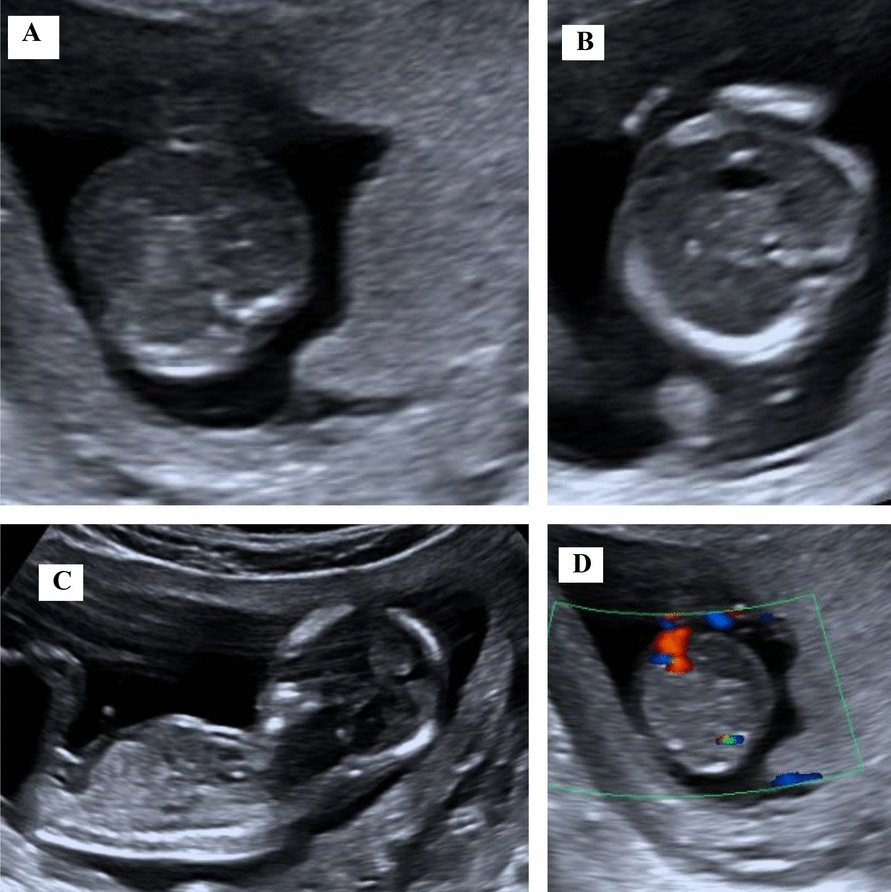

Case report: This report presents two cases: one of true omphalocele in a twin pregnancy and another of pseudo-omphalocele, underscoring the importance of careful assessment. The first case involves a twin pregnancy at 12 weeks' gestation, conceived through assisted reproductive technique in a 38-year-old Nepali woman of Indo-Aryan ethnicity. During a routine check-up, one twin was diagnosed with omphalocele. Trans-abdominal fetal reduction of the anomalous twin was performed. The other twin progressed to term and was delivered via cesarean section at 39 weeks. The second case involved pseudo-omphalocele, observed at 15 weeks' 3 days of gestation in a 32-year-old Nepali woman of Tibeto-Burmese ethnicity. Initially, the fetal abdomen appeared to herniate, mimicking omphalocele. However, a repeat examination after 30 min showed no herniation or defect. Retrospective analysis revealed that the misdiagnosis occurred because the fetal abdomen was compressed between the contracted myometrium and placenta.